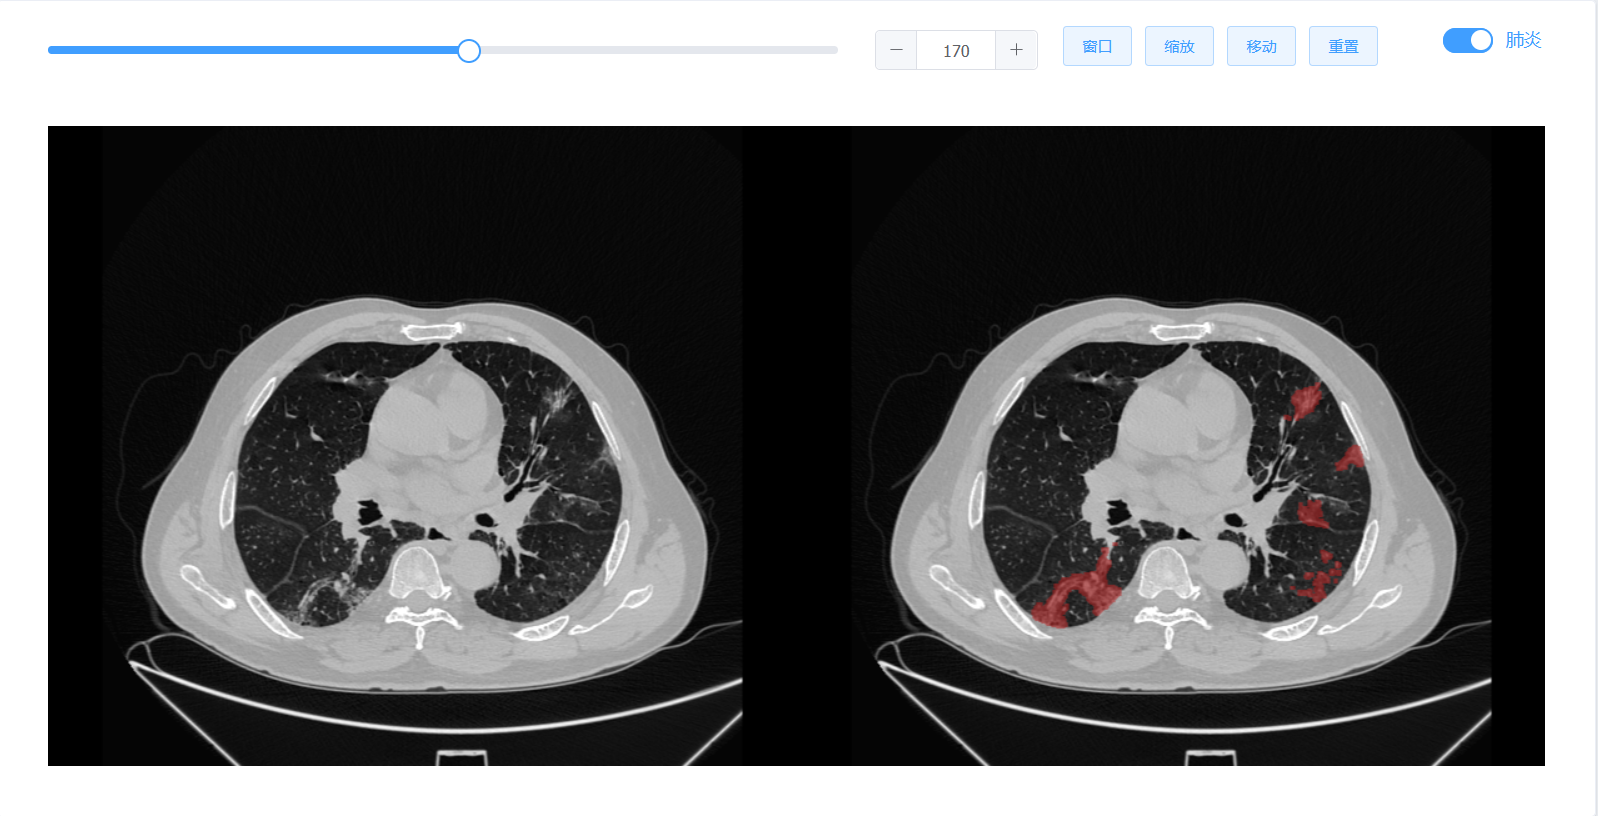

该成果研究了高精度快速多期新冠肺炎患者几何模型构建和定量分析算法,研究成果发表在医学影像顶级期刊TMI(IEEE TRANSACTIONS ON MEDICAL IMAGING,IF:10.048)上。目前该系统已经应用在张家界人民医院、哈尔滨医科大学附属第一医院等多家医院。经过科学对比和分析,该系统能够较好实现2分钟内多期新冠肺炎患者肺部器官和病灶的快速识别,并实现三维可视化,时间效率较目前常用影像建模软件提升30倍。极大提升了医生诊断的工作效率,同时能计算出肺炎体积,并进行定量分析,作为诊断的参考依据。该系统还能够支持多期医学影像数据协同管理,多人多机协同操作。